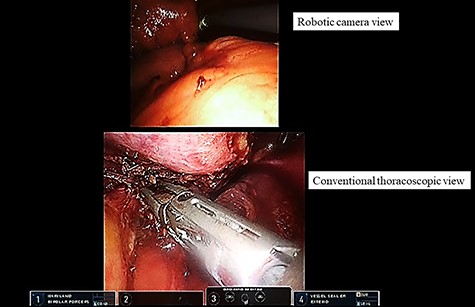

During robotic surgery, we divided the pericardium to gain an adequate surgical margin. However, the tumor itself was too large to observe the cranial and dorsal sides of the tumor as well as the intrapericardial space. We used conventional thoracoscopy to overcome this limitation. The thoracoscopic image was shown in the TilePro multi-display (Fig. 3). With the aid of both the robotic camera and conventional thoracoscope, the surgeon safely achieved complete resection of the tumor (Fig. 3). The tumor was retrieved via a subxiphoid incision. Finally, we performed pericardial reconstruction under robotic surgery.

Dual-scopic approach. With the aid of a dual-scopic approach using both a robotic camera and conventional thoracoscopic images, minimally invasive surgical resection of a challenging thymic tumor was achieved.

The dual-scopic robotic approach greatly contributed to the success of this surgery. Even under the robotic subxiphoid approach, the tumor sometimes limited the surgical field of view. In particular, the views of the cranial and dorsal sides of the tumor and the intrapericardial space were limited via the robotic camera because of the large tumor. Additional thoracoscopy provided a good view of the robotic camera’s blind side and thus enabled us to safely perform the robotic procedure. The dual-scopic approach is useful when performing challenging surgery.